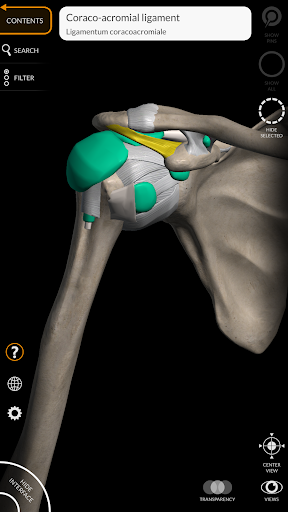

يتيح لك "Anatomy 3D Atlas" دراسة التشريح البشري بطريقة سهلة وتفاعلية.

من خلال واجهة بسيطة وبديهية، من الممكن ملاحظة كل بنية تشريحية من أي زاوية.

تتميز النماذج التشريحية ثلاثية الأبعاد بتفاصيل خاصة ودقة تصل إلى 4K.

• من خلال تحديد نموذج أو دبوس، يظهر المصطلح التشريحي ذي الصلة

وأضاف الأربطة